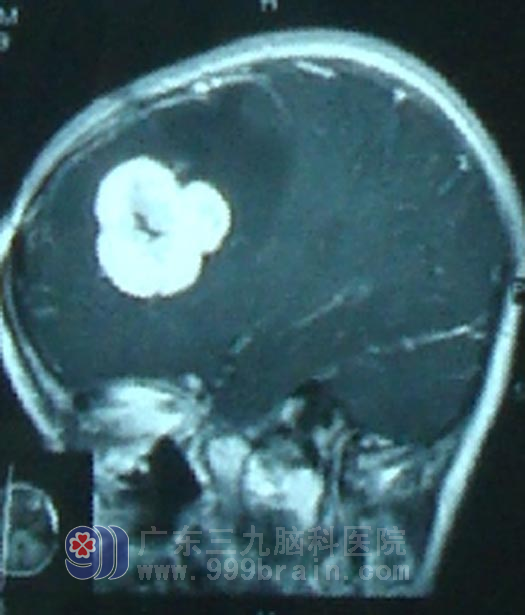

术前